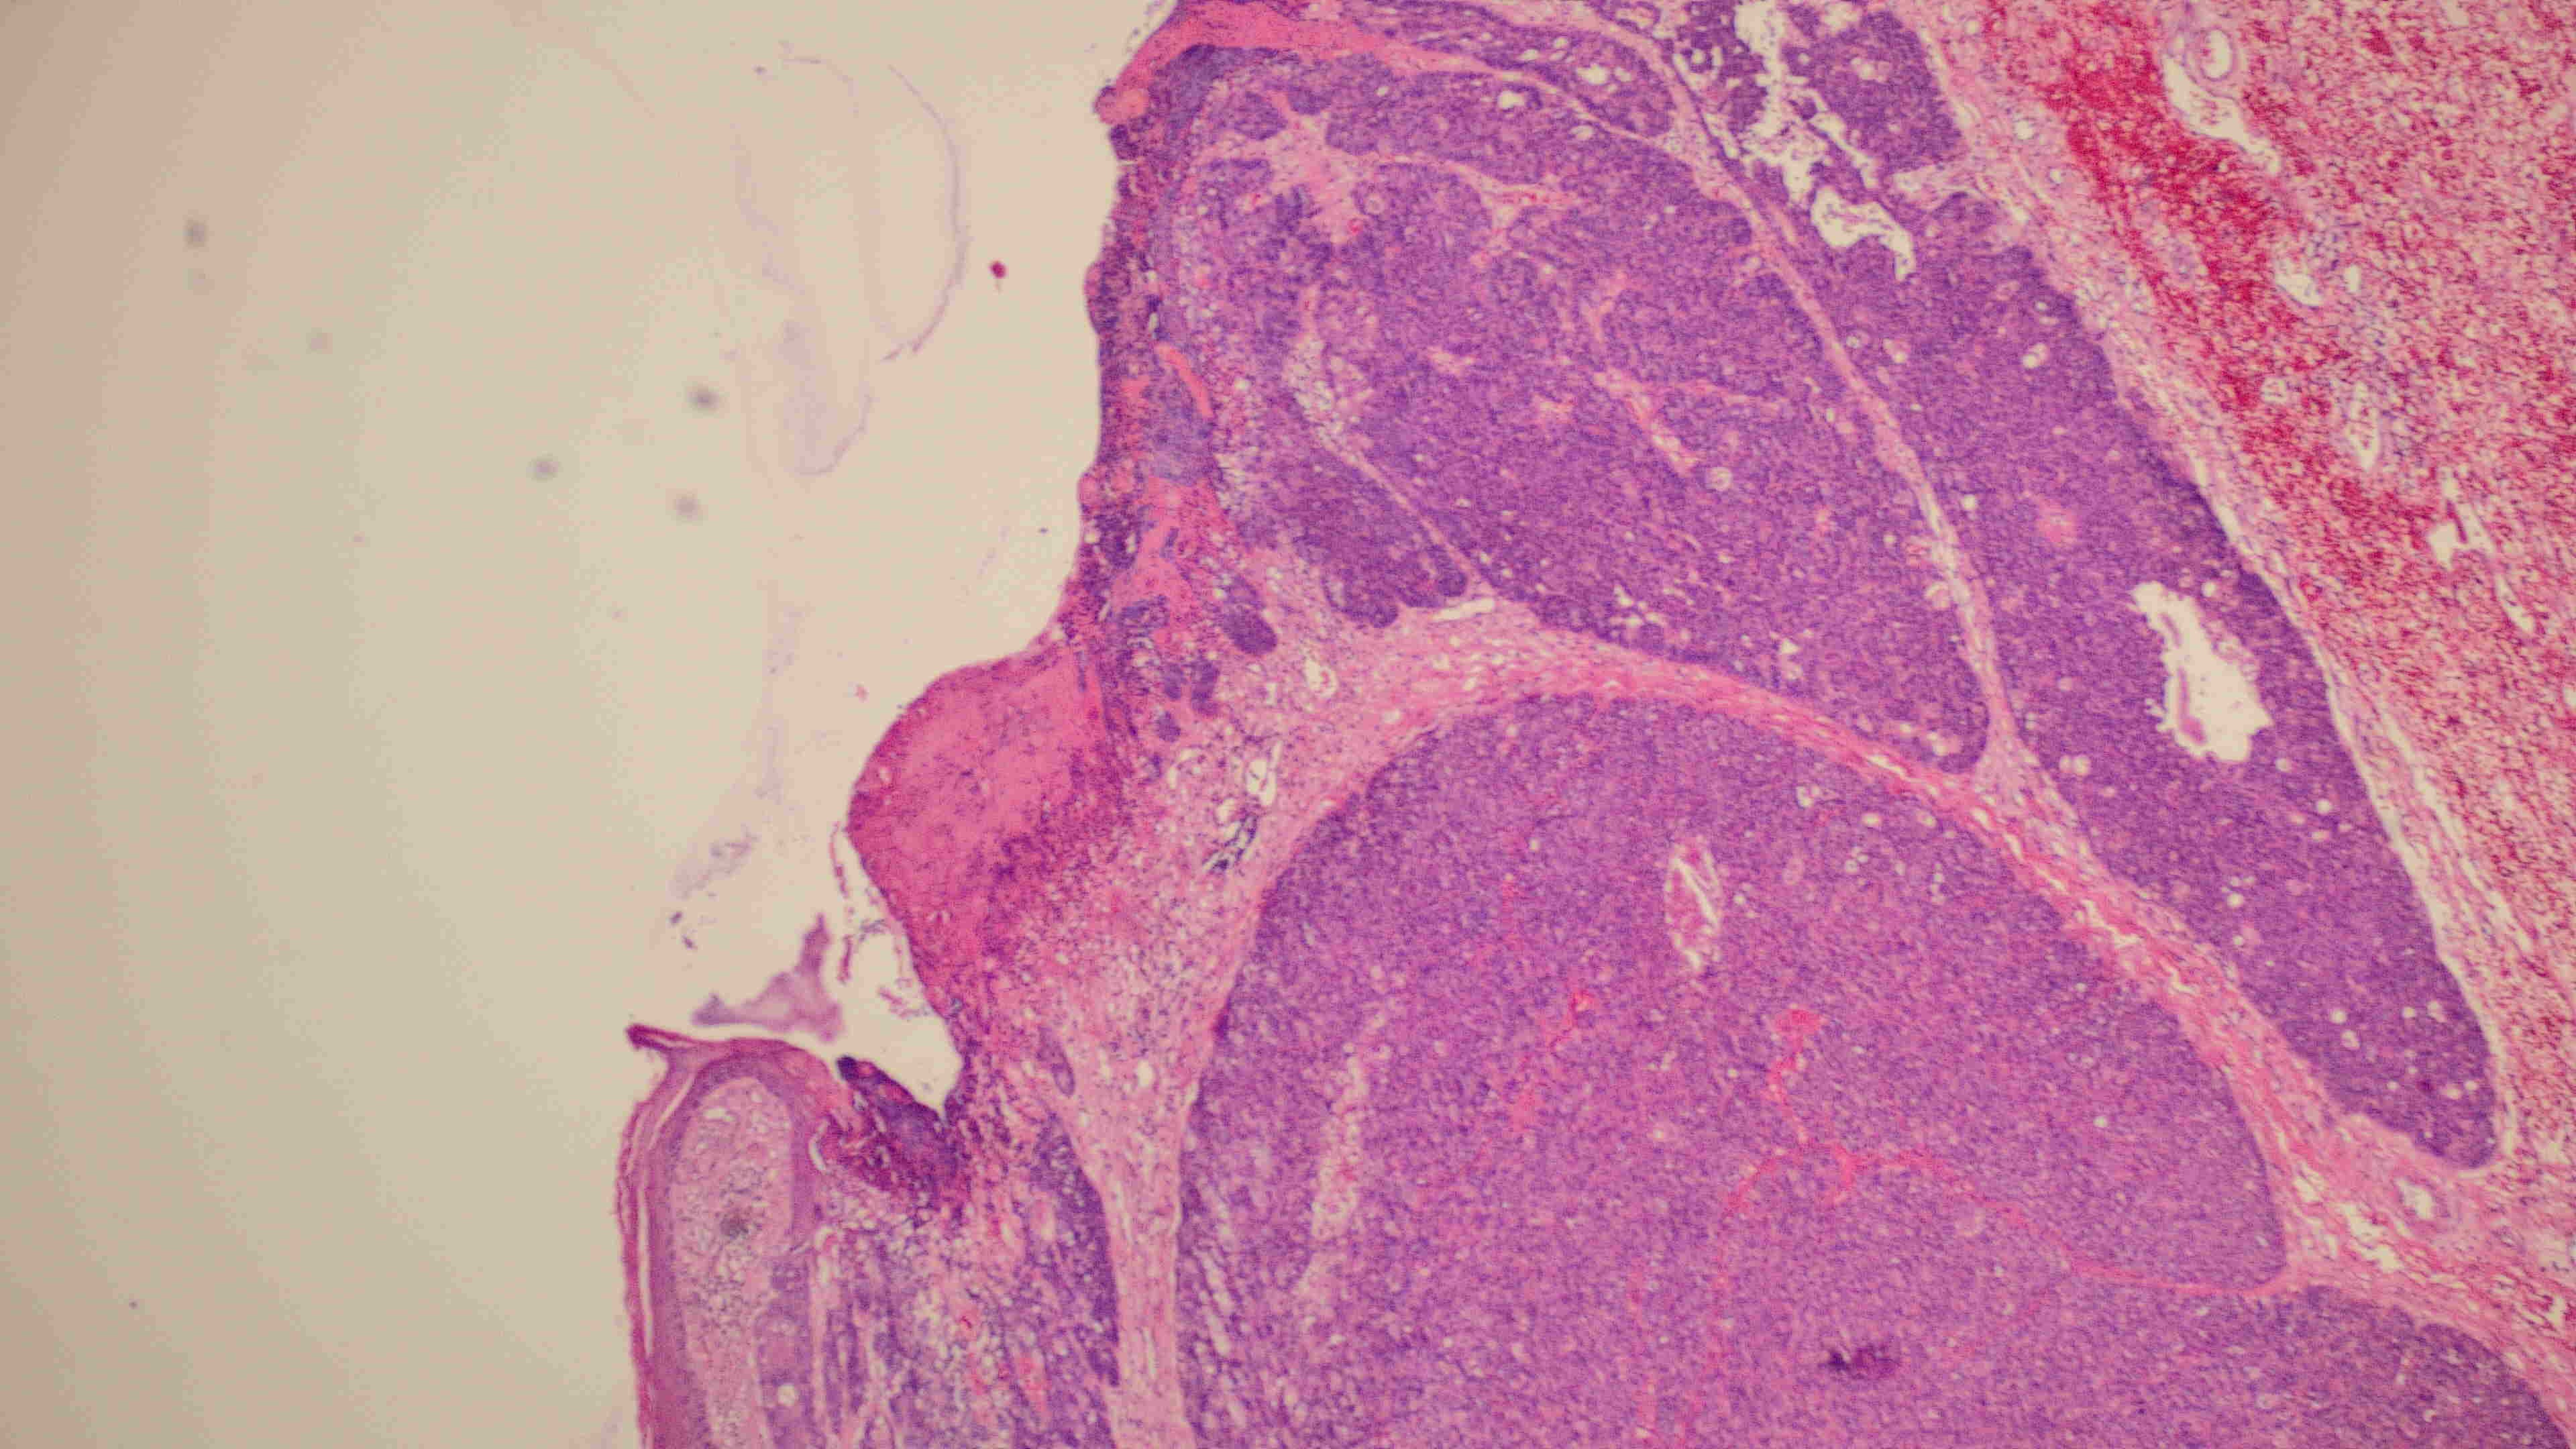

下巴肿物

带皮不规则组织3*3*2cm,切面灰白灰褐实性质软

会诊结果:小汗腺汗孔癌